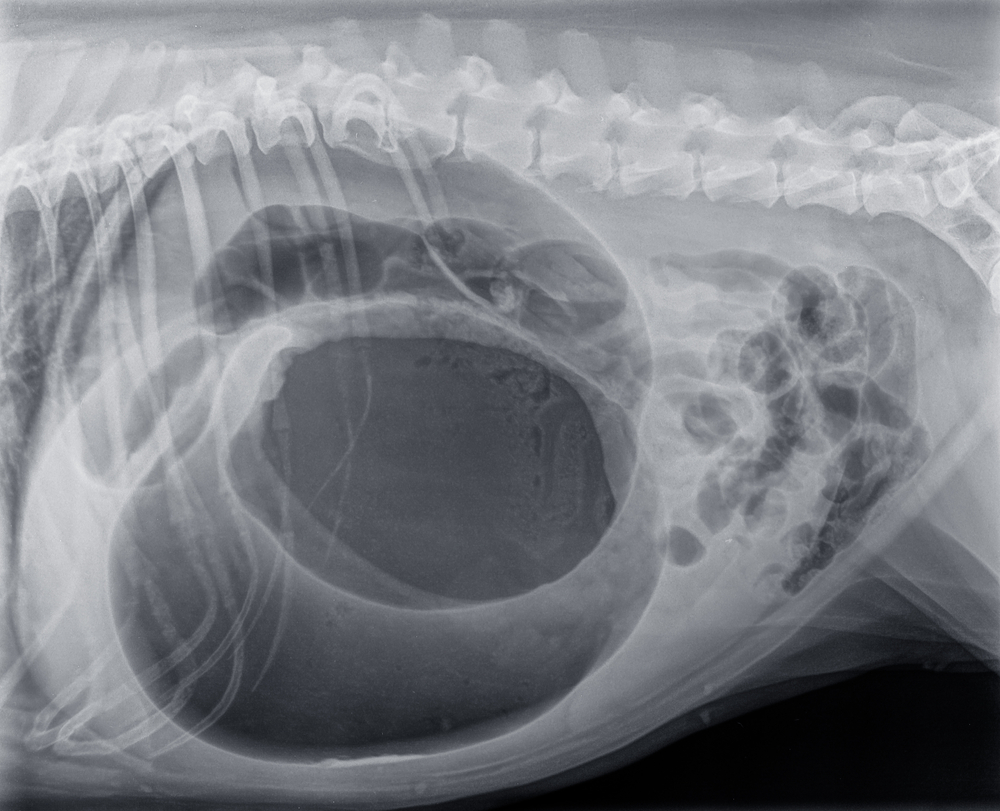

- X-rays — X-rays can help our West Vets Emergency Veterinary Clinic team determine if your dog’s stomach is twisted or only bloated.